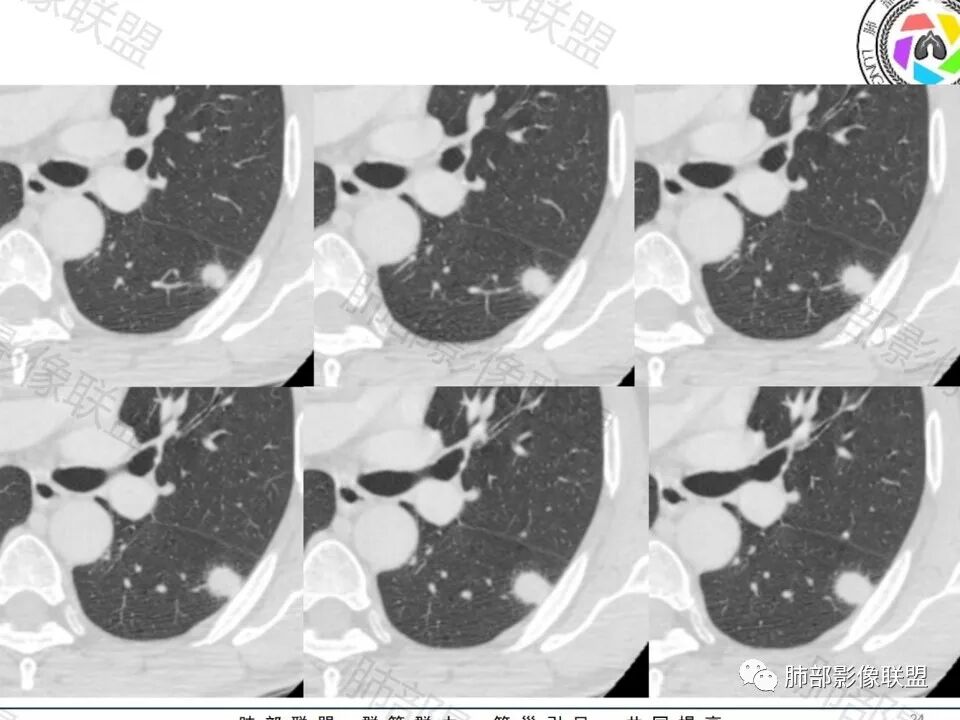

左肺下叶胸膜下结节,晕中毛刺,可见血管进入增粗,病灶中度均匀延迟强化,其他肺叶可见卫星病灶,考虑隐球菌。

男,60体检发现左肺下叶结节,左肺下叶类圆形结节影,边界清晰,边缘见浅分叶及细短毛刺,病灶内见增粗血管影穿行,相应层面胸膜增厚,双肺另见微小结节影,增强扫描病灶轻度强化,考虑隐球菌,除外腺癌。

老年男性,左肺下叶背段胸膜下孤立结节,整体圆顿,周围有晕,晕中毛刺,似乎支持隐球,但边缘有一囊腔,恶性不能除外!等答案!

支持腺癌,实变为主,周围有晕,血管穿过,考虑粘液腺癌可能性大

左肺下叶胸膜下类圆形结节,无分叶,无胸膜牵拉,周围有晕,血管支气管进入,考虑隐球菌

左肺下叶结节,边缘毛刺,见增粗血管影,临近胸膜增厚,腺癌可能。

真有一囊腔在结节边缘

这个腺癌确实要考虑了

左下肺、右中肺均有结节,左下肺病灶比较鼓,边缘有晕,血管弯,持续性强化,考虑腺癌可能,鉴别两处病灶如果一元论,肉芽肿炎 (隐球)

左肺下叶胸膜下实性小结节,边缘可见毛刺,轻度收缩,近端与血管束相连,远端轻度牵拉胸膜,并远端可见小空泡,平扫密度均匀,增强后渐近性强化,考虑腺癌,鉴别隐球菌

老年男性,CT左肺下叶胸膜下类圆形结节,边缘光滑,无分叶,可见毛刺,相邻胸膜多条牵拉,局部胸膜增厚,(多见炎性病变),病灶周围可见模糊晕征,血管支气管进入,考虑隐球菌,现实中万万不能排除肺癌。

中老年男性患者,无症状体检发现,胸部CT:左下肺内前基底段近胸膜下类圆形结节,边缘清晰,周围晕征,周围毛刺细软,有胸膜牵拉及血管进入,增强扫描明显不均匀强化,考虑炎性肉芽肿,隐球菌可能,鉴别腺癌

图做的真漂亮!老年男性,双肺多发结节,最大者位于左肺下叶胸膜下,周围有晕,晕中毛刺,边缘有一囊腔,胸膜牵拉,持续强化,考虑隐球,鉴别腺癌。

老年男性,查体发现,左肺下叶靠近胸膜下结节,边缘膨隆,胸膜牵拉,有细软毛刺,周围有空泡征?中度强化,有血管进入,收缩力不强感觉,我也考虑隐球菌,鉴别肺癌,粘液腺癌?

那根血管穿进去,短毛刺,老年,先癌后隐球菌

左肺下叶背段结节,短毛刺实性血管集束,增强富血供,不管病理最后怎么样,日常写报告考虑恶性腺癌可能大,建议手术或抗炎后无变化也建议手术。

左肺下叶胸膜下类圆形结节,边缘光滑,周围有晕,晕中有毛刺,周围可见小卫星灶,相邻胸膜增厚,血管进入,右肺中叶可见小结节影,考虑炎性肉芽肿,隐球菌。鉴别腺癌。

晨读:左肺下叶胸膜下实性小结节,边缘可见模糊晕及毛刺,轻度收缩,与支气管关系不清,近端与血管束相连,内见小空泡,平扫密度均匀,均匀强化。远近可见多个小结节。考虑炎性肉芽肿,隐球菌病,鉴别结核、腺癌。

老年男性,左肺下叶背段胸膜下结节,边缘毛刺,血管进入,斜裂有牵拉,局部胸膜糊墙,周围有晕,但有一囊腔,首先考虑腺癌,但是右肺中叶及左肺下叶还有其他结节,鉴别隐球菌

病史:男,60岁,体检左下肺结节,肿标阴性;

影像:轻微肺气肿,可能抽烟;旁边有个卫星灶4-5个,厚层无血管弯,薄层叶间裂轻度增厚,有囊腔,内侧有一个微血管,弯,另有两个微血管直,膨隆,增强血管不弯,糊墙,好像边界有些模糊,17-47-47,冠位轻度叶间裂弯。

诊断:警惕良性,隐球菌感染?

鉴别:腺癌,无磨玻璃,模糊?糊墙;纵膈窗太光滑,胸膜面广;不膨隆。支持点,薄层毛刺,强化。